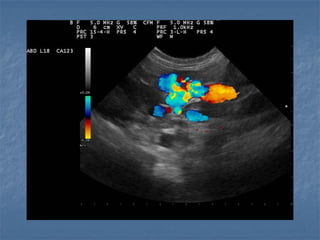

Alterações Vasculares

 ICCD

FÍSTULAS ARTERIOVENOSAS (ASCITE)